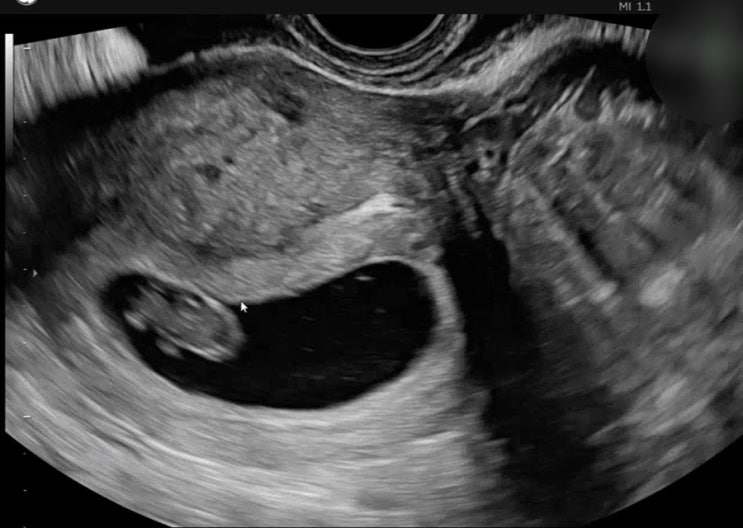

임신 8주차 이때 볼수있는 젤리곰!!! 보기위해 베스트오브미여성의원에 갔다 아직 난임병원을 다니는 중이...

난임일기/자연주기-4일배양/아기집확인,출산예정일

2차 피검까지하고 드디어 아기집 확인하러 다녀왔다 ! 얼마나 떨리던지 아기집은 잘 컸는지 난황은 생겼는...